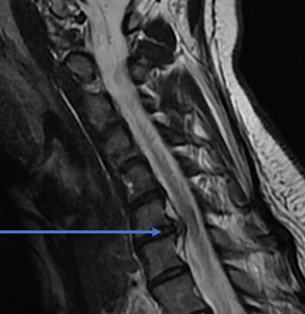

32 year old female comes with right arm pain that radiates all the way down to her fingers. We tried therapy, injections, oral pain medicine, and time. Because of the pain, a MRI showed a herniated disc in her neck on the right side (arrow). The left image is a side view and the right images is a cross section view.

She underwent a minimally invasive anterior cervical discectomy and fusion after removing the herniated disc. A MRI shows resolution of the herniated disc.